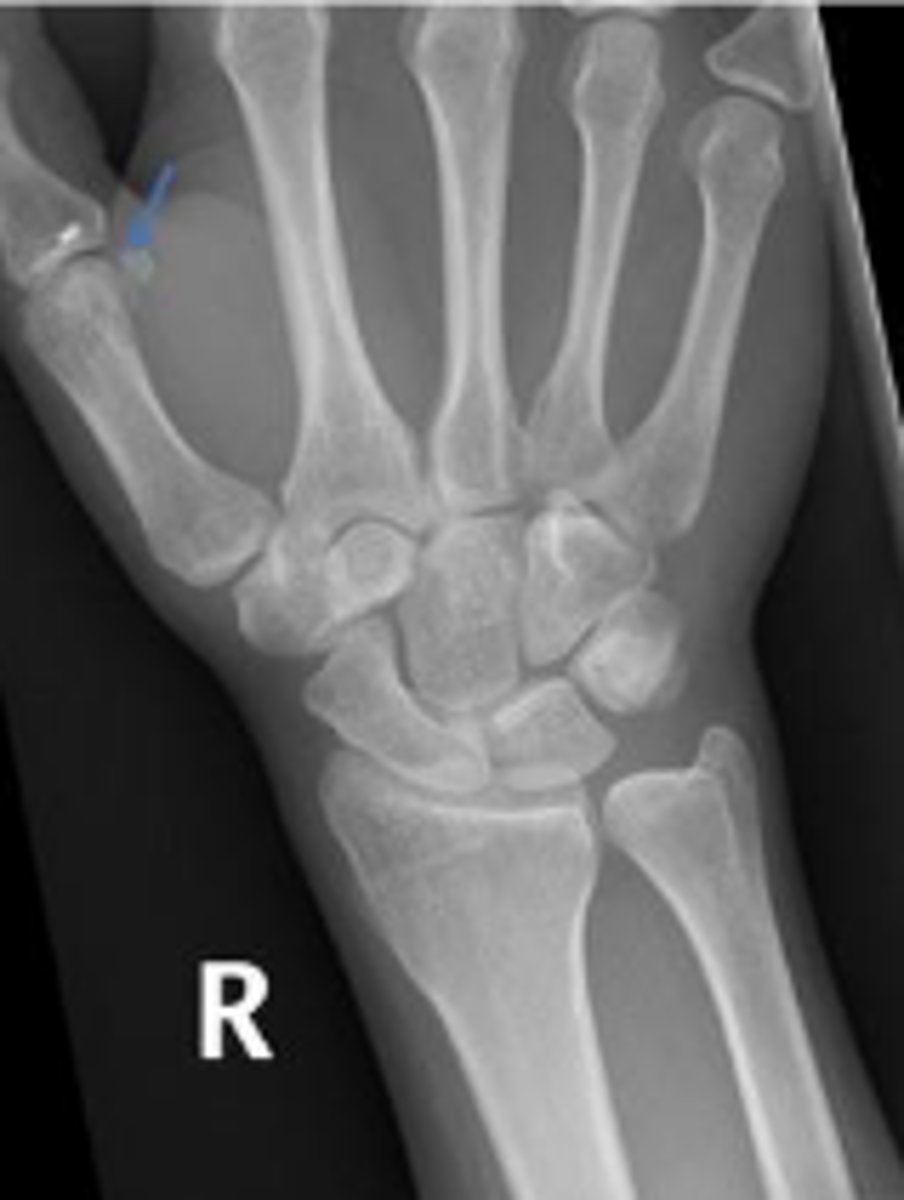

PA right wrist

What is the name of the radiographic view?

Sesamoid bone

What is the arrow pointing to?

Right trapezium

What is outlined?

Right triquetrum

Right pisiform

What is the arow pointing to?

Right trapezoid

Right capitate